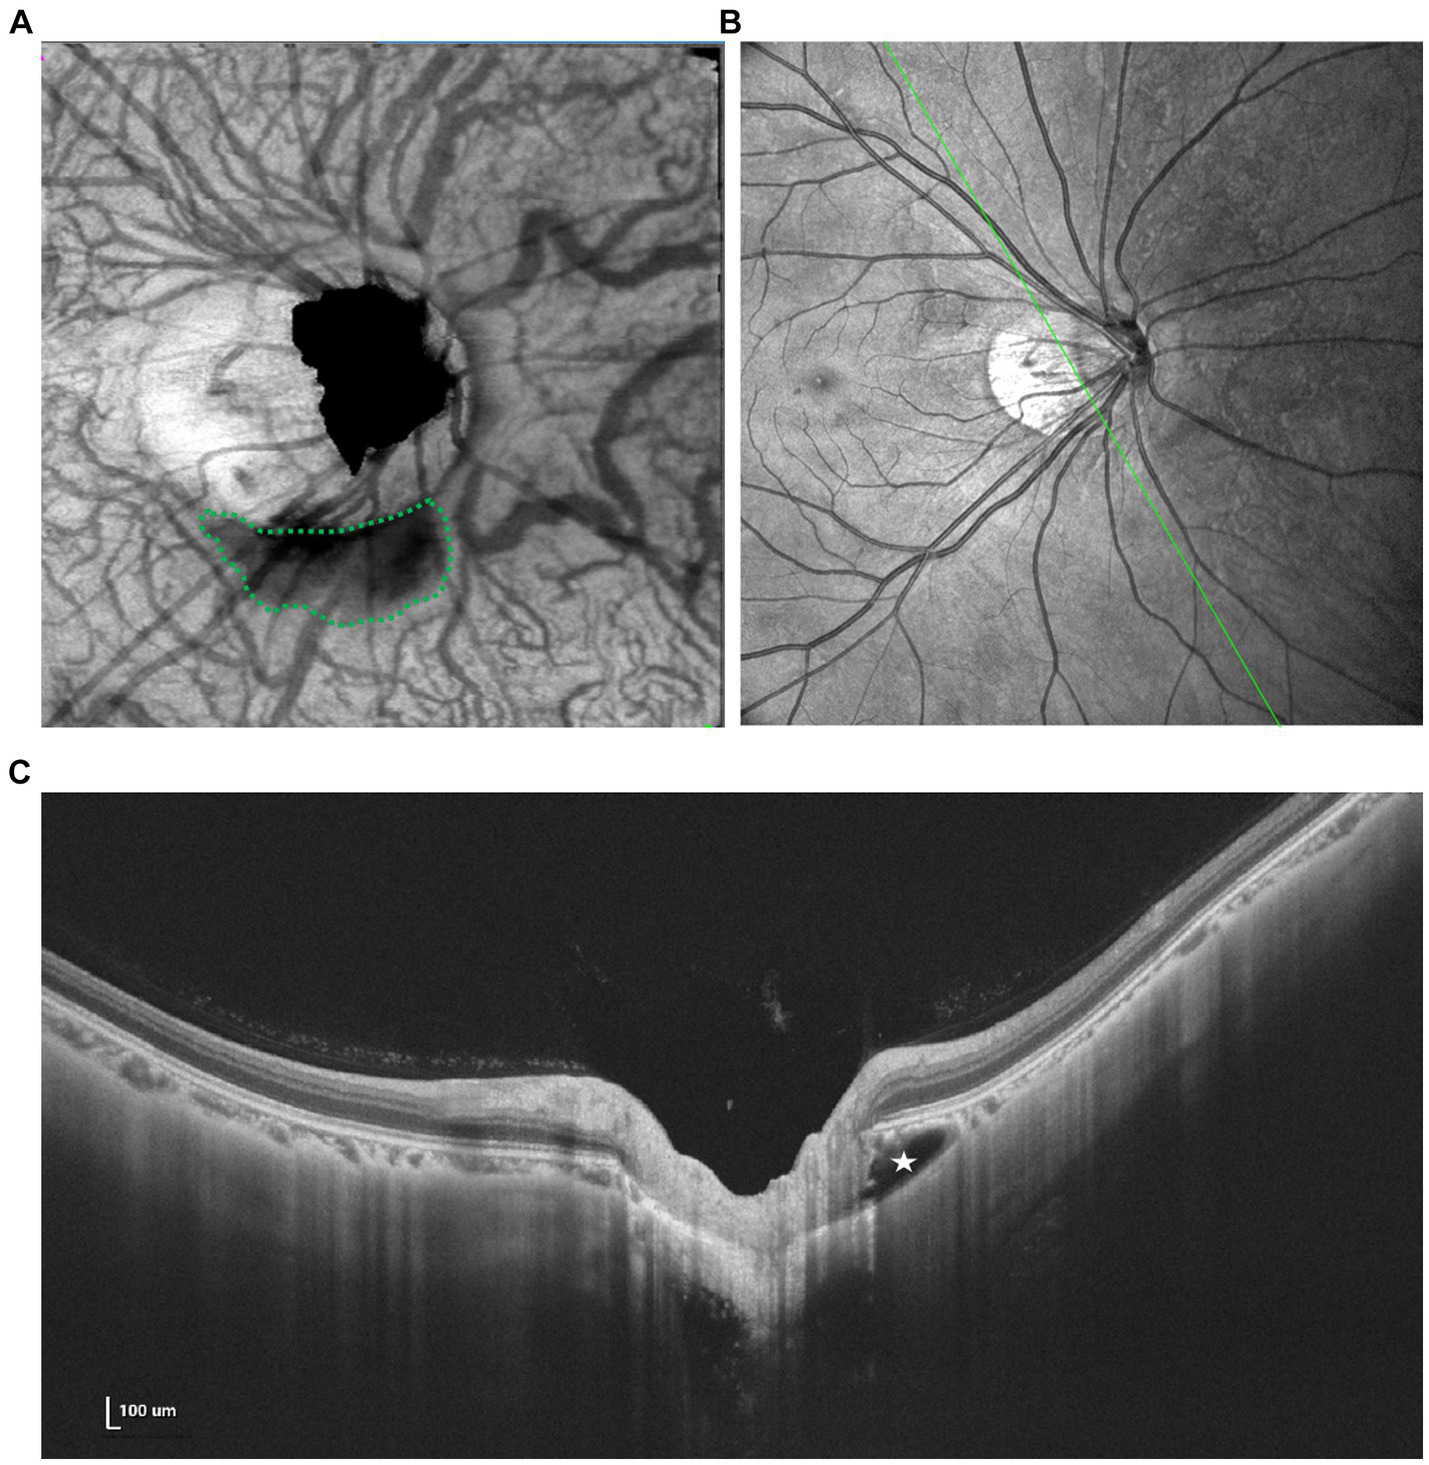

Based on OCT manifestations, PICC is characterized as a hyporeflective triangular thickening of the choroid with the base at the optic disk border in horizontal or vertical sections, occasionally displaying discontinuity of the normal overlying RPE (49, 50) (Figure 4).

Figure 4

Multimodal imaging of PICC. (A) En face image shows an irregular hyporeflective area (green dots) inferior to the optic disk. (B,C) Spectral domain OCT revealed a large intrachoroidal hyporeflective space below the normal RPE plane within the PICC (white star).